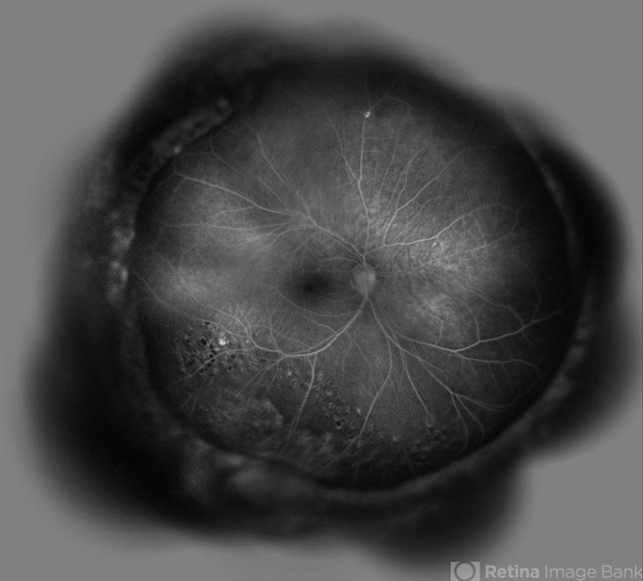

Labbafinejad Medical Center - Uploaded on Jul 7, 2015.

- Nayereh Hadipour, Negah Eye Center,Tehran, Iran

- Specteralis

- Late FA image of the right eye of a 30-year-old man who underwent pars plana vitrectomy , endolaser photocoagulation and an encircling band placement a couple of years before following a penetrating trauma at the vitreous base area at the 7 o'clock meridian.